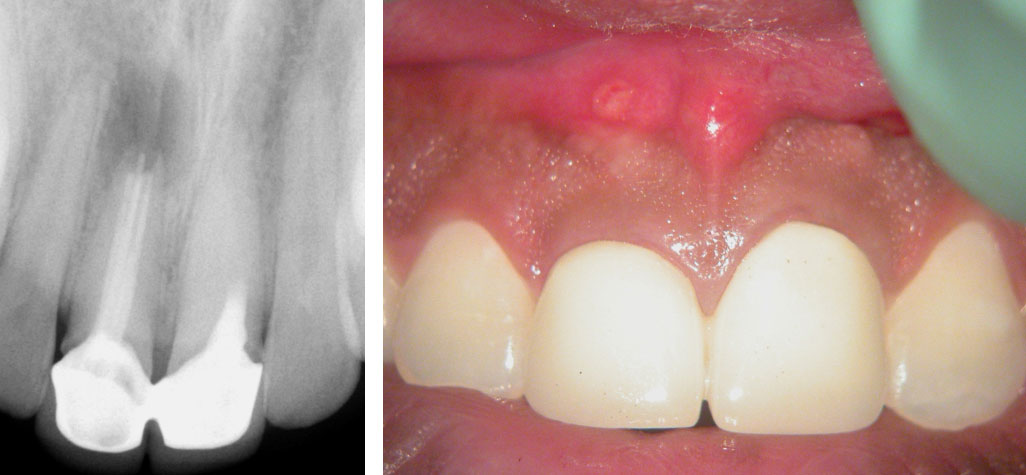

Pre-op

Persistent pain and swelling over the right central Incisor. Pain on palpation over the left central incisor. History of previous root canals and surgery done 3 years ago.

Treatment Plan:

(Patient in town for only 9 days)

• Putty impression. Remove crowns.

• Left Central incisor: Remove old filling. Locate calcified canal. Repair perforation if present. Do obturation and core build-up

• Right Central Incisor: Remove old filling. Fill entire canal with MTA. Core build-up with Composite.

• Refer to Prosthodontist to prep and take impressions for new crowns. Cement temporaries.

• Surgical Curettage of lesion and Apicoectomy of right central incisor.

6 days later, Suture removal and Cement Permanent crowns.

Left Maxillary central Incisor

Canal located

Perforation repaired with MTA

Obturation and core build-up done.

Pre-op, Canal location & Post-op